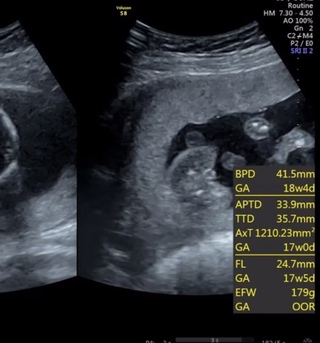

Sep 05, 19 · 女の子の性別判定はいつから可能? 女の子の性別判定はいつから可能なのでしょうか? 男の子も女の子も外性器がしっかりと形成され、 性別判定ができるようになってくるのは大体どちらも早くて妊娠16~17週目くらい と言われています。 が、女の子の性別判定は残念ながら男の子に比Jun 05, 16 · 妊娠16週5日(16w5d)で性別がわかった! 妊娠16週5日(16w5d)のエコー画像 妊娠16週で性別が男の子と確定したエコー画像 PR出産準備が10%オフ!Amazonベビーレジストリに登録しよう! 流産リスクなしの出生前検診って知ってる?男の子 16週 エコー 性別 見分け方男の子 16週 エコー 性別 17週のときのエコーです!これは男の子のシンボルでしょうか エコー写真男の子の性別診断☆私の場合は17週で発覚 2人目が初男の子。

16週 エコー 性別 見分け方-Sep 01, 17 · 赤ちゃんの性別は受精の時点で決まっていますが、見た目ではっきりと区別できるようになるのは妊娠11週頃とされています。 (※1) しかし、それをエコー検査で確認できるようになるのは早くても妊娠17週~18週頃からです。 (※1)Oct 29, · # 性別;

16週 女の子 エコー写真 16週 エコー 突起物 女の子 ~ すべての エコー写真 性別の見分け方 男の子女の子別エコー 妊娠週まとめてみ 16週0日16w0d女の子yu0215ki さん29歳 エコー写真撮影時のエピソード パパも一緒にエコー見た 始めてのお腹からのエコー私よりパパの方が興奮してたo赤ちゃんは元Mar 22, 17 · エコーの 性別の見分け方 です。 これはしっかりとお勉強して 次の健診に活かしましょう。 男の子の見分け方 男の子は女の子よりわかりやすいです! 足と足の間にあるポコっとでている ピーナッツのようなものがみえたら それがおそらくシンボルです。ただいま妊娠15週です🥺 エコー写真で性別わかる方 いましたら教えてほしいです😌 このエコー写真でわかるか わかりませんが😫😫🤍 妊娠16週目(16w)のエコー写真を見てみると、胎児の大きさは、CRL(頭殿長)が108~116mm、体重は80gほどに成長。

Jul 19, 19 · 男の子の性別判定はいつから可能? 男の子の性別判定はいつから可能なのでしょうか? 男の子の性別判定は比較的早く、早くて15週・16週ごろからシンボルが見えてくる ようです! 私の場合、1人目の男の子が17週で性別ほぼ確定となりました。妊娠16週で、早くも性別がわかったので、エコー画像をまじえて報告いたします( ´ ` )ノ 妊娠16週で性別がわかるとは思ってなかったので、とっても嬉しい!お医者さんに聞いたところ、条件がととのえば妊娠16週で性別がわかるんですって。 17週0日。Aug 30, 17 · 妊娠16週から妊娠5ヶ月、そして妊娠中期に入ります。早ければ子どもの性別がわかる時期なので、ママもパパもドキドキしますね。お腹の赤ちゃんの大きさは80g~1gほどになり、胎動を感じることも。もう耳も聞こえているようです。今回は、コズレ読者の方にお送りいただいた妊娠16週

Jan 14, 18 · そこで今回は赤ちゃんの性別がわかる妊娠週数と男女の見分け方についてお話します。 赤ちゃんの性別の判断は割と単純です。エコーで赤ちゃんの様子を見ながら判断します。 妊娠16週の妊婦健診を目安に性別を聞くSep , · ジンクス的(お腹の膨らみ方、顔つきといった人によって印象が違うもの)を除き、11~12週頃の横向きのエコー写真で判別する「Baby nub」という判別方法があるそうです。ダウン症のエコー特徴 手足・頭・BPD・NT・FL徹底解説 Down 妊娠16週2日(16w2d)の超音波(エコー)写真;